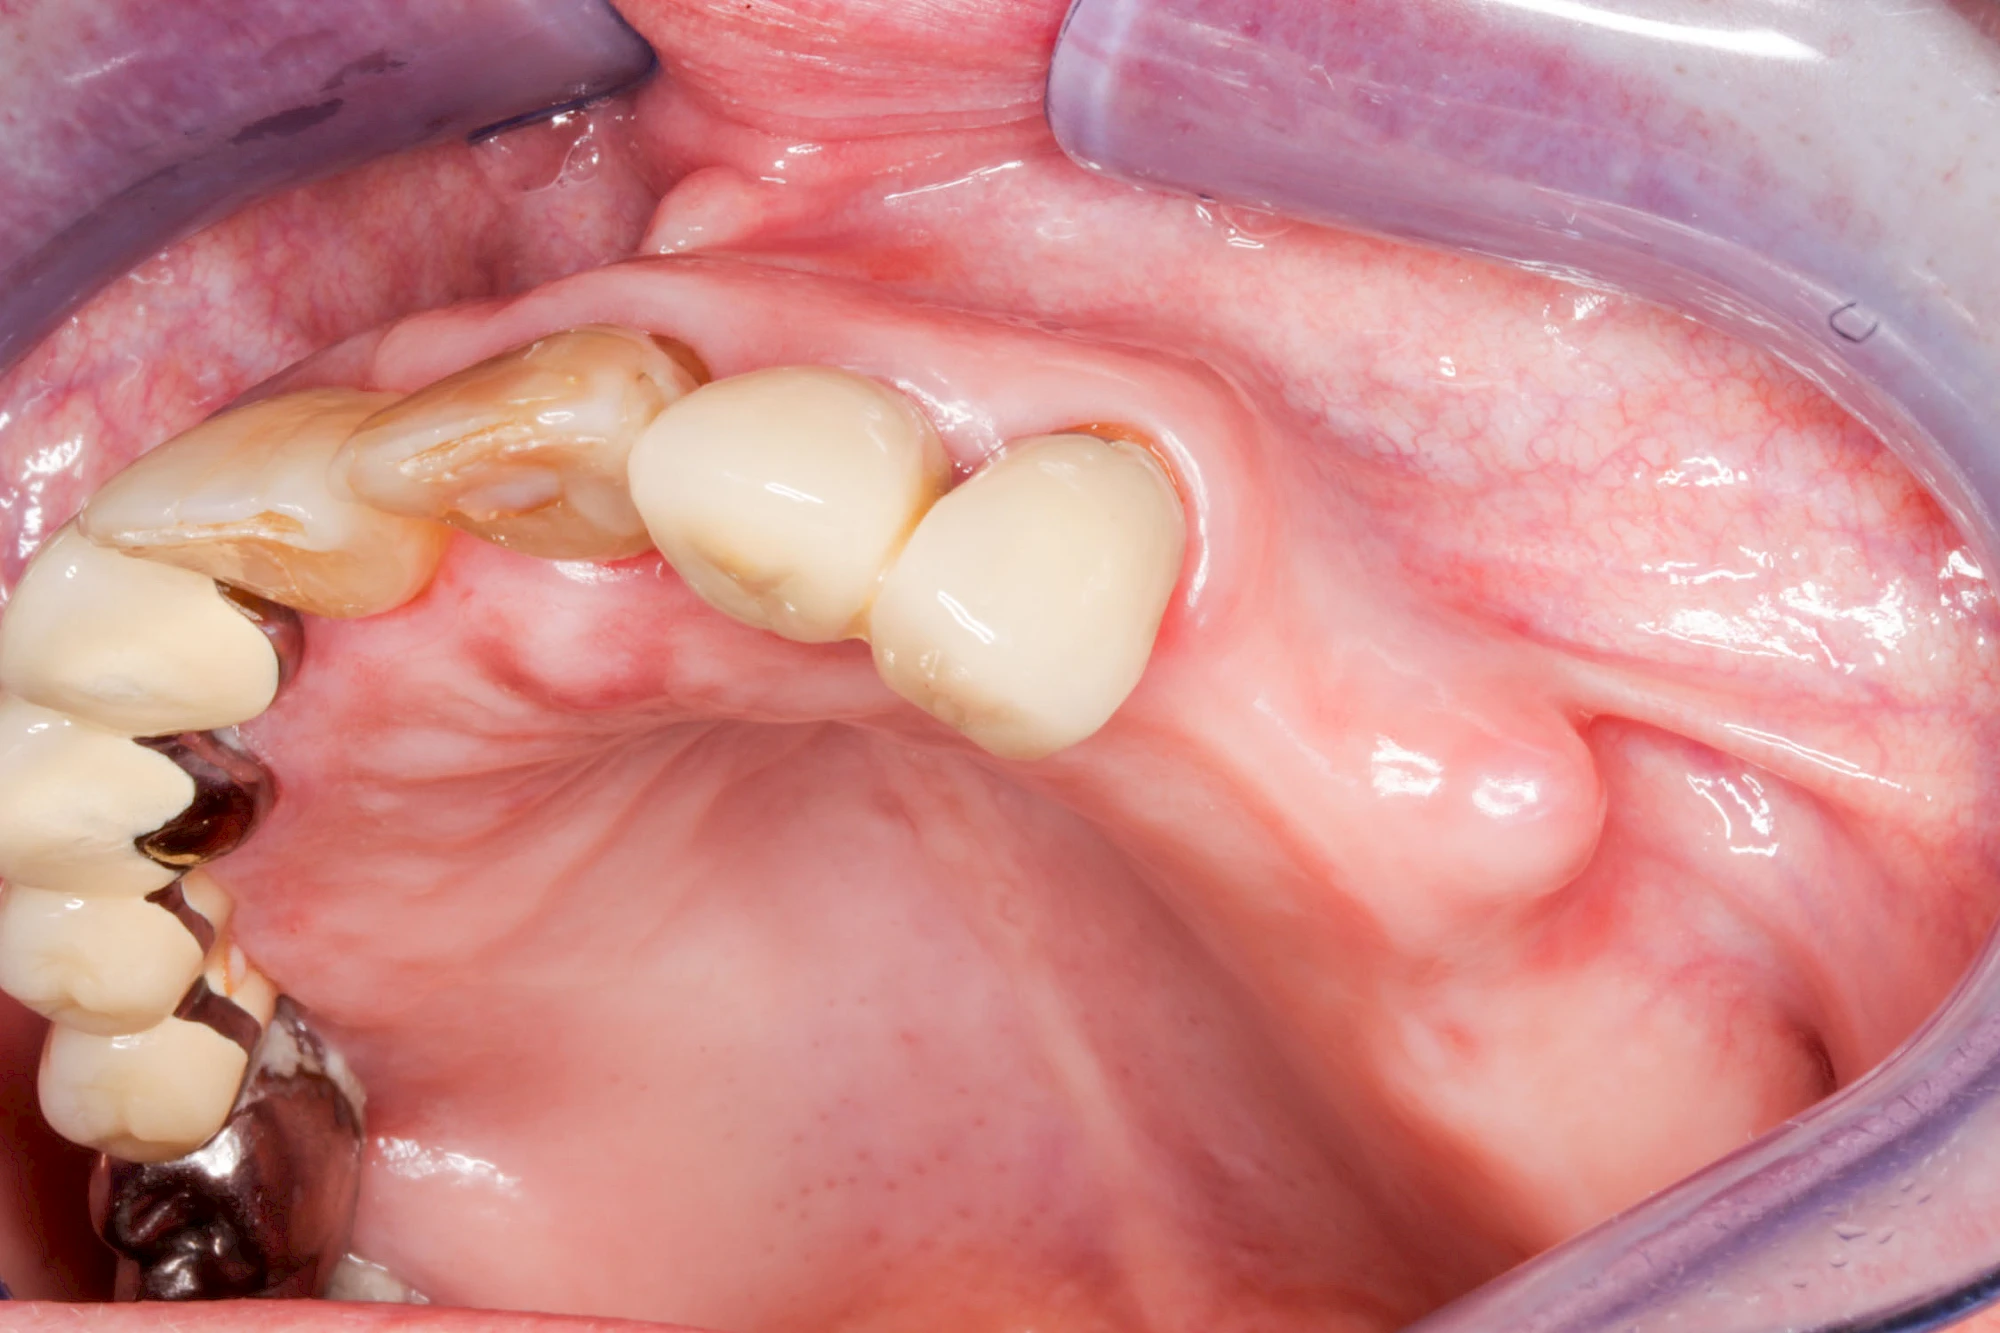

Lippen-Kiefer-Gaumenspalten (LKG-Spalte) sind angeborene Fehlbildungen im Mund-Kiefer-Gesichtsbereich. Die Gewebestrukturen im Bereich des Oberkiefers sind im Zuge der Entwicklungen bis zur Geburt nicht zusammengewachsen. Diese Fehlbildung zählt zu den häufigsten Fehlbildungen des Menschen, von 500 Neugeborenen ist eines betroffen. Die Fehlbildungen können sich auf Lippe, Gaumen und Kiefer allein beschränken, treten häufig aber kombiniert und in seltenen Fällen sogar beidseits auf.

Heute werden in Deutschland Menschen mit Lippen-Kiefer-Gaumenspalten bereits ab Geburt von Experten verschiedener Fachrichtungen (Mund-Kiefer-Gesichtschirurgen, Kieferorthopäden, Logopäden) betreut, damit entsprechende Korrekturen schon frühzeitig erfolgen können. Gerade jedoch bei älteren Menschen ist dies nicht immer geschehen. Diese Menschen tragen häufig technisch aufwendige Zahnprothesen.